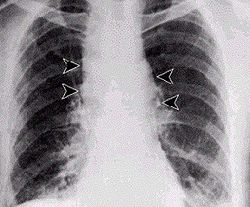

多為原發性,也可繼發於皮膚炭疽。初期為輕微的上呼吸道感染,低熱、乾咳、肌痛。數天后病情急驟加重,表現為高熱、寒戰、呼吸急促、喘鳴、發紺、咯血樣痰、大汗和心率增速,頸、胸部可有皮下水腫。肺部可聞及散在的細濕囉音和捻發音,可有大量胸腔積液。體徵與病情嚴重度不成正比。X 線除顯示肺炎外,胸腔積液,典型表現為縱隔增寬。患者病情大多危重,常並發敗血症和感染性休克,也可繼發腦膜炎,表現為劇烈頭痛、嘔吐、抽搐、昏迷,有明顯腦膜刺激症。血性腦脊液可檢出炭疽桿菌。

其他輔助檢查:X線表現除顯示肺炎外,胸腔積液,典型表現為縱隔增寬。